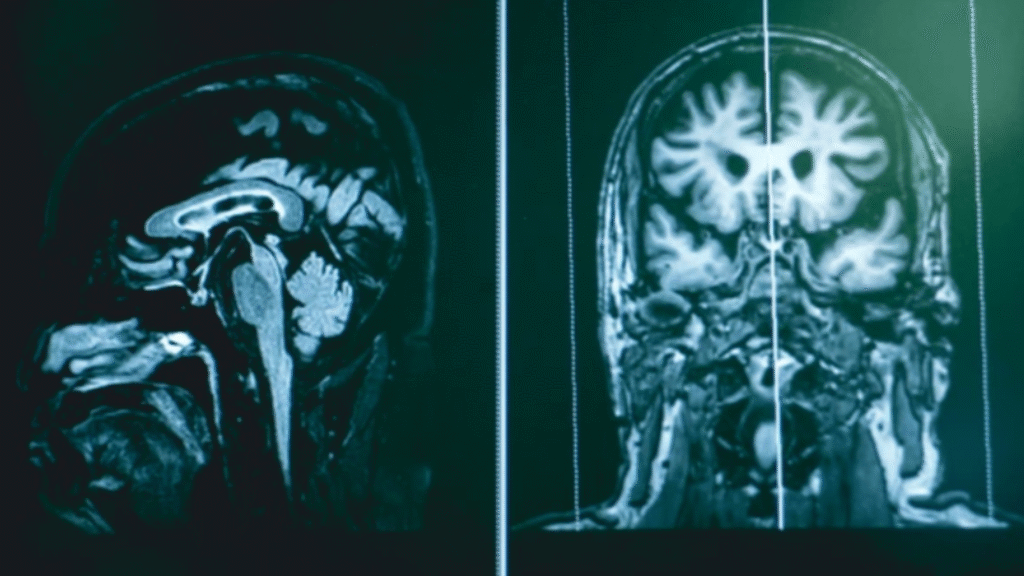

MRI brain scans displayed side by side showing cross-sectional views.

Source: Unsplash

James referenced actor Bruce Willis, who was diagnosed with frontotemporal dementia, as a comparison point. That parallel intensified backlash, with critics calling it irresponsible to equate public speaking errors with a confirmed degenerative disease. Frontotemporal dementia typically presents with significant behavioral and language impairment that progressively worsens, often confirmed through neurological imaging and clinical evaluation.